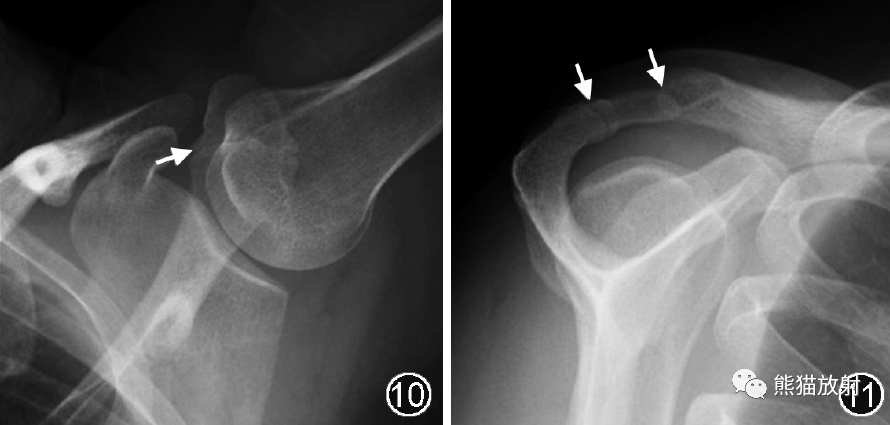

肩峰次骨化中心通常在22~25岁骨化完成,如果骨化中心未能如期愈合,未愈合的部分就称为肩峰小骨,在X线腋轴位或CT/MR横断面上观察最佳,在冈上肌出口位或CT/MR的斜矢状面上有时可见“双肩锁关节征”(图10, 11, 12)。

图10,11 肩峰小骨的X线片。腋轴位(图10)示肩峰见透亮线影,边缘少许硬化,其走行与肩锁关节大致垂直(↑),考虑为肩峰小骨;冈上肌出口位(图11)可见“双肩锁关节征”(↑)